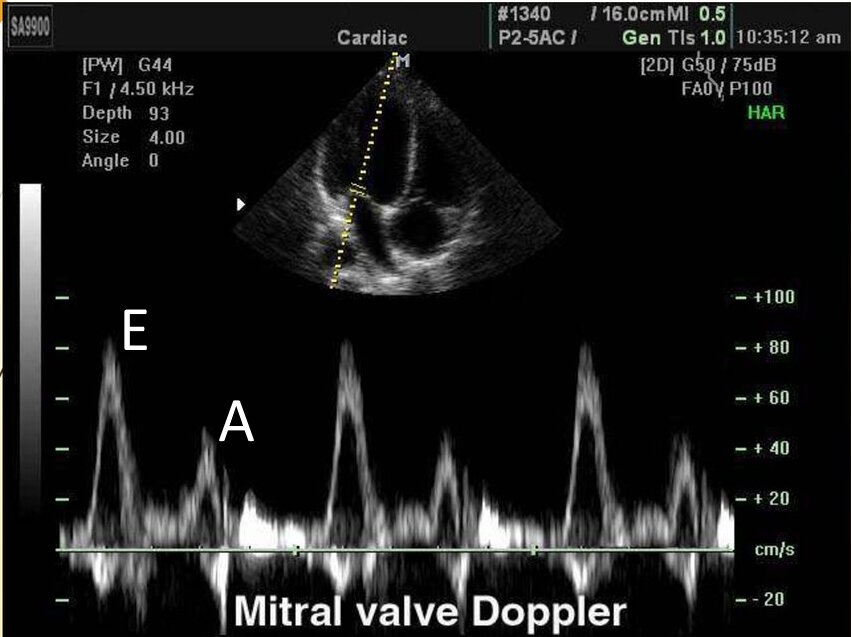

Собственно, какой показатель на УЗИ отражает диастолическую функцию сердца? Для этого врач должен включить доплеровский режим и поставить датчик, например, на митральный клапан. И увидеть следующее:

Большой треугольник называется "пиком Е", а маленький "пиком А". В идеале у молодых людей соотношение E/А должно быть выше 1,5. Чем старше человек, тем меньше это соотношение, т.е. пик Е становится постепенно меньше пика А.

Подобная картина говорит уже о нарушении расслабления сердца, т.е. E/A ниже 0,8. Развивается диастолическая дисфункция, приводящая к значительному ухудшению здоровья.

Соотношение E/A снижается с возрастом. Но что удивительно даже у молодых людей, которые не переносили инфаркты, можно увидеть уменьшение пика Е. И наоборот, у 50-ти летних отличные показатели.